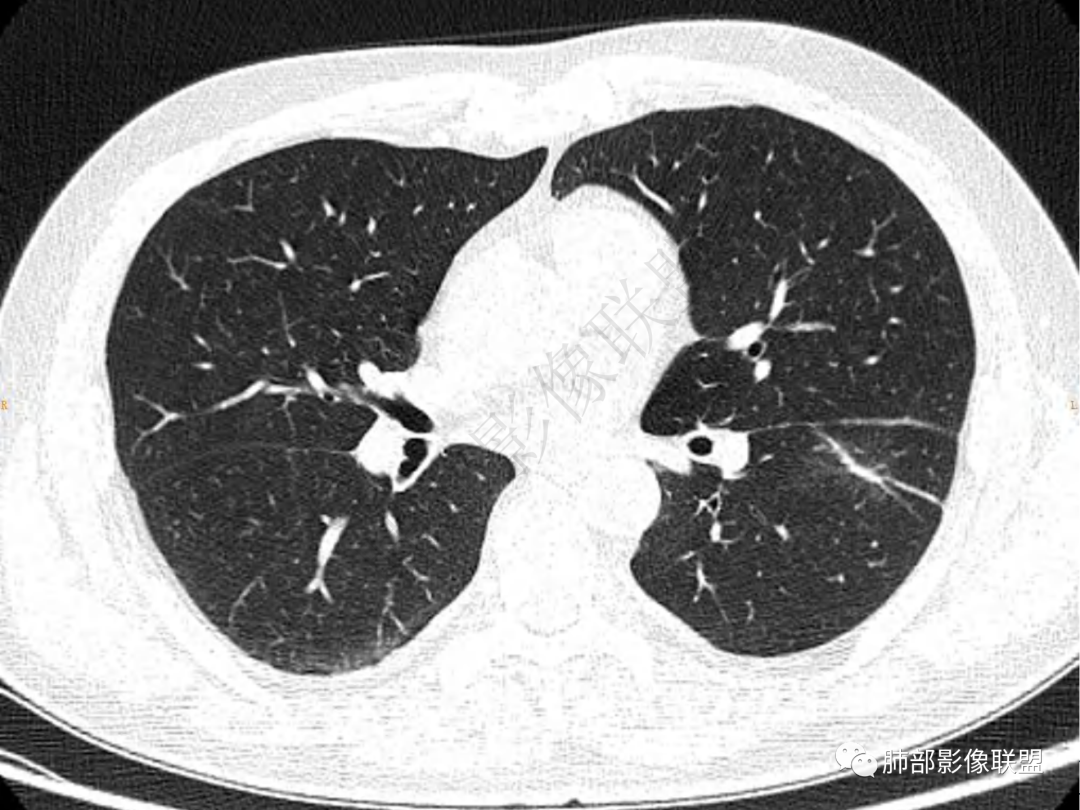

2.左肺下叶团片影,跨背段及内前基底段,实性部分类椭圆形,密度不甚均匀,可见毛刺及棘状突起,未见典型分叶及胸膜凹陷。病灶上下缘可见相应肺段支气管旁进侧出,管壁轻度增厚,未见狭窄阻塞。

3.周边较大范围磨玻璃影,边界相当模糊,小叶增厚明显。注意叶裂另一侧、左肺舌段亦可见磨玻璃影及增厚的小叶间隔。未见明确卫星病灶。

5.双肺门及纵隔未见增大淋巴结。未见胸腔积液。